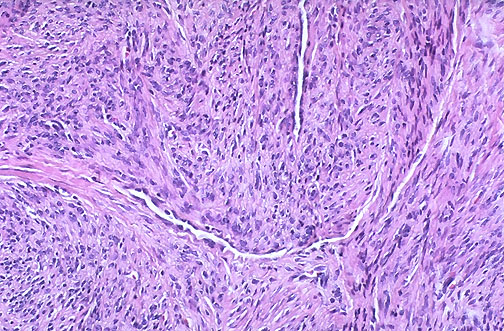

| Desmoid tumors are poorly demarcated and invade surrounding soft tissues, so they must be excised with a wide margin. Microscopically, they are composed of fibroblastic cells in a collagenous stroma. There can be some pleomorphism and a rare mitotic figure. |